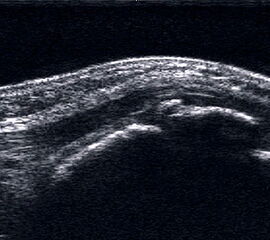

Fußsohle

Fasziitis plantaris, unterer Fersensporn, M. Ledderhose

Lagerung: Bauchlage oder Schneidersitz.

Schnittführung: Plantarer LS vom Fersenbein nach distal.

Referenzstruktur: Kalkaneus.

Befunde: Die plantare Fasciitis stellt sich als echoarme Verdickung im Insertionsbereich der Plantarfaszie am vorderen unteren Anteil des Fersenbeins dar. Eine Auftreibung von mehr als 6 mm gilt als pathologisch.

Der knöcherne Fersensporn ist als längliche echogene Ausziehung mit Schallschatten erkennbar. Manchmal findet sich auch eine lokale echoarme Bursaverdickung. Bei chronischer Veränderung mit Übergang in eine Teilruptur wird die Struktur der Plantarfaszie zunehmend inhomogen. Ein akuter Einriss imponiert als Konturunterbrechung, teilweise gewellter Verlauf bei Spannungsverlust und echoarmes Hämatom welches sich bis in die kurzen Fußbeugemuskulatur ausdehnen kann.